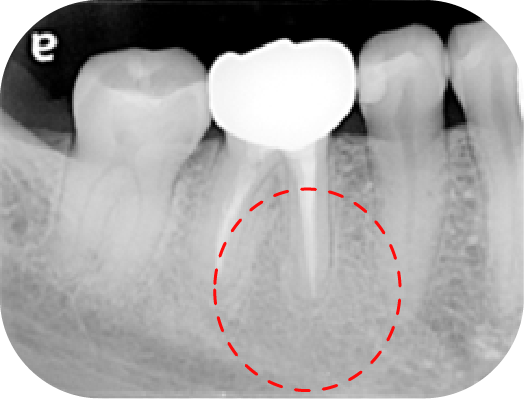

案例分享

左圖中第一大臼齒兩個牙根皆因為根管內的感染造成根尖周圍炎(紅線中黑黑的地方),在根管治療後追蹤一年可發現骨頭都已經恢復正常的樣子

上圖中第一大臼齒兩個牙根皆因為根管內的感染造成根尖周圍炎(紅線中黑黑的地方),在根管治療後追蹤一年可發現骨頭都已經恢復正常的樣子